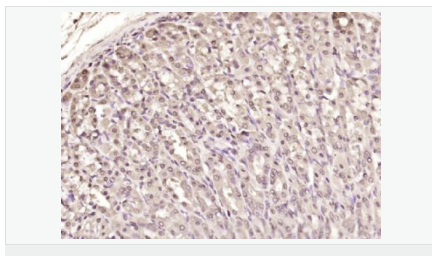

| 產(chǎn)品應(yīng)用 | WB=1:500-2000 ELISA=1:5000-10000 IHC-P=1:100-500 IHC-F=1:100-500 Flow-Cyt=1μg/Test ICC=1:100 IF=1:100-500 (石蠟切片需做抗原修復(fù)) not yet tested in other applications. optimal dilutions/concentrations should be determined by the end user. |